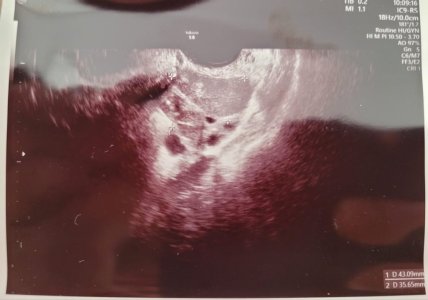

Ekteki dosyalarda yumurtalıklarımın ultrason fotoğrafı var. 3 tane yumurta görünüyor. tüp bebek merkezi 20ye yakın yumurta olduğunu, yumurta toplama işleminin güzel geçeceğini söyledi ama bu ultrason fotoğrafı kafamı karıştırdı. ilk denememdeki gibi 3 yumurta toplanırsa moralmen çökerim. Diyelim iyi yumurta toplandı, çikolata kisti için cerrahi müdahale yumurtalık rezervine olumsuz etki yapıyor. bu durum beni korkutuyor. Doktor kendinden çok emin konuştu. Güvenmek istiyorum ama güvenemiyorum. Tedaviye başladık bir kere. Ama çok kararsızım. Sizce cerrahi müdahale yaptırayım mı?

Ultrason filmi çikolata kistini tespit eden doktora ait.

Ekteki dosyalarda yumurtalıklarımın ultrason fotoğrafı var. 3 tane yumurta görünüyor. tüp bebek merkezi 20ye yakın yumurta olduğunu, yumurta toplama işleminin güzel geçeceğini söyledi ama bu ultrason fotoğrafı kafamı karıştırdı. ilk denememdeki gibi 3 yumurta toplanırsa moralmen çökerim. Diyelim iyi yumurta toplandı, çikolata kisti için cerrahi müdahale yumurtalık rezervine olumsuz etki yapıyor. bu durum beni korkutuyor. Doktor kendinden çok emin konuştu. Güvenmek istiyorum ama güvenemiyorum. Tedaviye başladık bir kere. Ama çok kararsızım. Sizce cerrahi müdahale yaptırayım mı?

Ultrason filmi çikolata kistini tespit eden doktora ait.